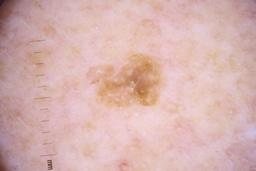

ISIC_4077341

- Challenge 2020: Training

- IP_1969685 IL_9238622

Clinical

| Field | Value |

|---|---|

| acquisition_day | 1 |

| age_approx | 50 |

| anatom_site_1 | Trunk |

| anatom_site_2 | Anterior trunk |

| concomitant_biopsy | False |

| dermoscopic_type | contact non-polarized |

| diagnosis_1 | Benign |

| diagnosis_confirm_type | serial imaging showing no change |

| family_hx_mm | False |

| image_type | dermoscopic |

| lesion_id | IL_9238622 |

| patient_id | IP_1969685 |

| personal_hx_mm | True |

| sex | male |